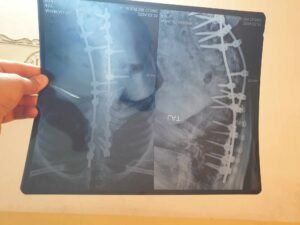

بعد التواصل مع الاسرة المتعففة، المتكونة من (زوجين واولادهم الاربعة)، وبعد التقييم الشامل لاحتياجاتهم الأساسية، تبين ان الاب يعاني من انحراف ولادي في العامود الفقري وما زاد صعوبة المرض عليه اجراء عمليه فاشله في الهند بعد ان باع كل ما يملك لإجرائها.  كما انهم لا يملكون ابسط المتطلبات المنزلية وكذلك بدل الايجار بالإضافة الى الأدوية والعلاجات التي تكلف 200 الف دينار شهريا.

نظرا لإمكانيات (منظمة طريق الرحمة)  المحدودة قررت التكفل بالأدوية  والعلاجات لمدة (شهرين) قابلة للتمديد حسب التبرعات والمساعدات وبالقدر الذي تسمح به إمكانات وظروف متطوعي منظمتنا.